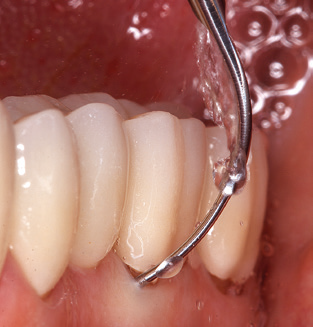

The current working concept for SPT

Fig. 4: Flexible probes with millimetre markings are recommended for the probing of dental implants (e.g. Colorvue Kit PCV11KIT6, Hu­Friedy). – Fig. 5a and b: A straight working tip (1P, W&H Dentalwerk Bürmoos GmbH) is a suitable instrument for use on all natural teeth. – Fig. 6: Curved working tips (3Pr/3Pl, W&H Dentalwerk Bürmoos GmbH) lend themselves to the processing of difficult-to-reach areas of the tooth and root surfaces (e.g. furcations). – Fig. 7: The tapered, hexagonal implant cleaning tip (1I, W&H Dentalwerk Bürmoos GmbH) permits atraumatic and efficient cleaning of the crown and abutment surfaces. – Fig. 8: Titanium and carbon curettes are suitable instruments for the manual cleaning of the implant surfaces.

Good illumination of the working field facilitates the process considerably. The system used by the authors achieves this thanks to a 5x LED ring integrated in the handpiece. Naturally, a range of working tips for different indications is also offered. A straight, universally employable tip is the basic instrument required for machine cleaning of natural teeth (Fig. 5a and b). Curved tips, which allow access to exposed furcations, are also available for hard-to-reach areas in the posterior region (Fig. 6).